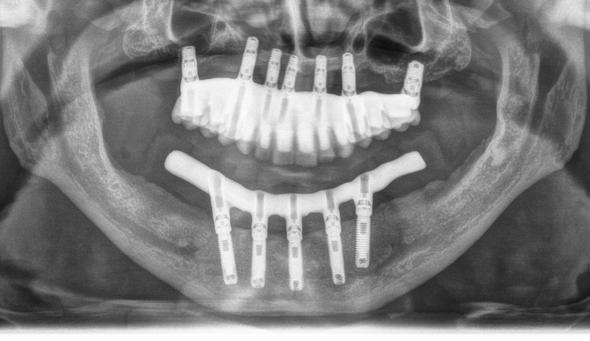

Figura 1. Diámetros y longitudes incluidos en el estudio según su posición.

Figura 2 y 3. Figuras intraorales del paciente de 67 años que acude a la consulta para rehabilitación sobre implantes superior, portador de una prótesis completa removible con una atrofia ósea evidente al ser la prótesis retirada. Figura 4. La radiografía inicial muestra una atrofia marcada en sentido vertical, que debe ser constatada posteriormente mediante un TAC así como para la planificación de la colocación de los implantes. Figura 5 y 6. Encerado diagnóstico para comenzar la planificación de la colocación de los implantes superiores guiados por la posición ideal que deben tener los dientes en la prótesis. De este encerado se realiza una guía radiológica que nos permita trasladar estas posiciones al TAC de planificación.

Fueron reclutados 6 pacientes en los que se colocaron 30 implantes para realizar rehabilitaciones completas. La edad media de los pacientes incluidos en el estudio fue de 66.75 años (+/- 5,16) y un 86.7% fueron mujeres. El 63.3% de los implantes se insertaron en el maxilar superior y el 36.7% restante en la mandíbula, formando parte de 4 rehabilitaciones

completas superiores y 3 inferiores. Todos los implantes presentaron una longitud de 5.5 m m, con diámetros comprendidos entre los 2.5 y los 5.5 mm. Las posiciones de los implantes corresponden a distribuciones biomecánicas para la realización de prótesis completas tanto en el maxilar como mandíbula (incisivos, premolares y molares). Los diámetros y longitudes de los implantes incluidos en el estudio en función de

181. Septiembre 2023 51 Rehabilitaciones completas implantosoportadas

su posición se muestran en la Figura 1.

Figura 7­9. Cortes de planificación del cone beam donde observamos la extrema atrofia vertical y la posición en la que deberían situarse los dientes con una gran discrepancia entre esta posición y la base ósea. Vemos también como se planifican implantes extracortos de 5.5 mm de longitud en todas las localizaciones. Figura 10. Radiografía panorámica tras la colocación de los implantes.

En las Figuras 2­17 se puede observar uno de los casos incluidos en el estudio.